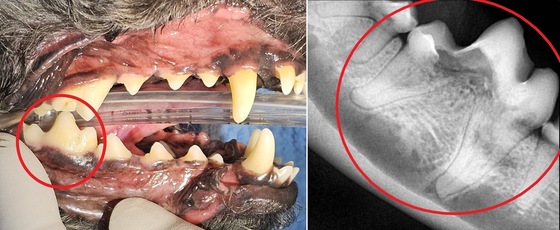

이러한 방향성은 진료 현장에서 더욱 분명하게 드러난다. 라라동물의료원은 치과 진료 시 모든 환자에게 치과 엑스레이와 CT(컴퓨터 단층촬영) 검사를 시행해 눈에 보이지 않는 치근 상태까지 확인한다. 검사와 치료는 마취하에 연속적으로 진행되며 사전 상담을 통해 보호자가 치료 과정과 범위를 충분히 이해할 수 있도록 돕는다.

이 원장은 "겉으로 멀쩡해 보여도 치아 뿌리가 이미 손상된 경우가 적지 않다"고 설명했다.

겉으로 멀쩡해 보였던 반려견의 어금니 치아, 건강검진 시 치아 엑스레이를 찍은 결과 치아 내부가 녹아 있었다(병원 제공). © 뉴스1

실제로 최근 내원한 반려견은 외관상 큰 문제가 없어 보였다. 보호자가 신경 써서 양치 관리를 꾸준히 해온 반려견이었다. 그런데 엑스레이 검사에서 어금니 치아 내부가 녹아있었다. 결국 어금니를 발치해야 했다.

이 원장은 "음식을 먹을 때마다 통증을 느꼈을 것"이라며 "겉으로 보이는 상태만으로는 판단하기 어려운 영역"이라고 설명했다.